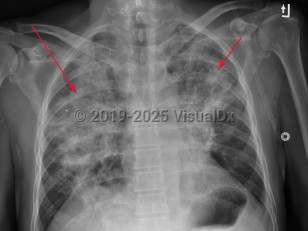

Herpes simplex pneumonia (HSP), or tracheobronchial infection, occurs when the respiratory tract is infected with the herpes simplex virus (HSV). HSP typically occurs in immunosuppressed patients such as those who are neutropenic from chemotherapy, immunosuppressed following organ transplantation, or are immunocompromised from HIV/AIDS or other immunodeficiency diseases. HSP has also been reported in patients who are not immunosuppressed. In most instances, infections were related to other risk factors such as smoke inhalation, recent major surgery, coexisting bacterial pneumonia, or airway injury from intubation. HSP is reported in all ages from infants and children to extreme old age.

Symptoms of HSP include dyspnea, fever, and nonproductive cough. Symptoms can be mild to severe; some patients can have a smoldering course with minimal fever. HSP is treatable with acyclovir but can be life threatening.